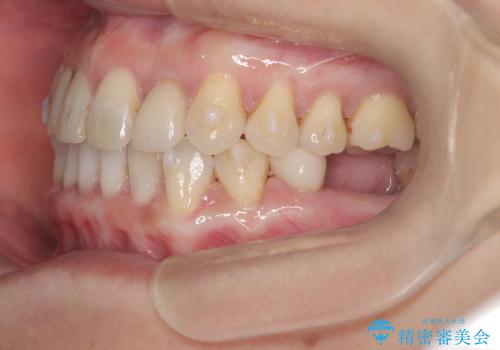

- 歯と歯の間に大きなスペースがある「空隙歯列(すきっ歯)」と、一部の歯が欠損していることによる噛み合わせの不安定さを主訴にご来院されました。

精密検査の結果、全体の隙間を閉じるだけでは適切な咬合バランスが得られないため、まずはインビザラインを用いて歯の位置を理想的な場所へと整える計画を立案しました。矯正によって欠損部位に適切なスペースを確保した後、その部分にインプラントを埋入することで、審美性と機能性の両立を目指しました。

治療は、まずインビザラインを使用して全体の隙間を閉じつつ、将来インプラントを入れるためのスペースをミリ単位で精密に調整しました。マウスピース矯正は、歯の移動量をデジタルで管理できるため、最終的な被せ物の大きさに合わせた理想的な位置取りが可能です。